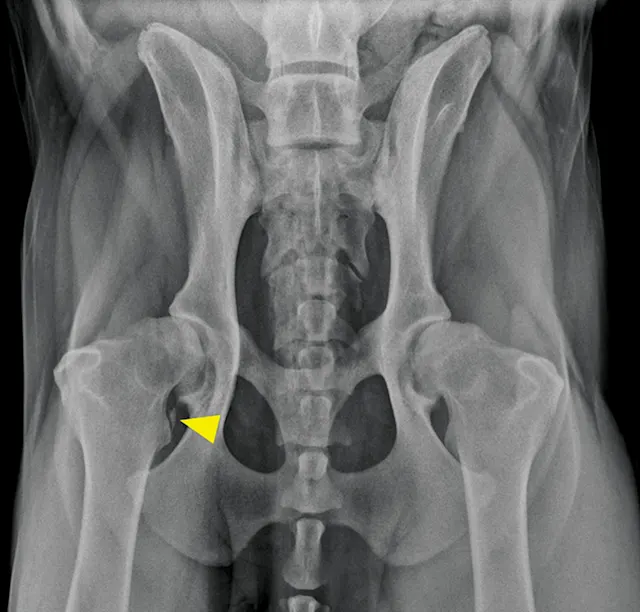

Ventrodorsal radiographic projection of a 9-year-old dog with right hindlimb lameness and hip pain. In addition to bilateral hip dysplasia and secondary osteoarthritis, mineralization is present within the right iliopsoas muscle near the tendon insertion on the lesser trochanter (arrowhead), which indicates a chronic strain injury.